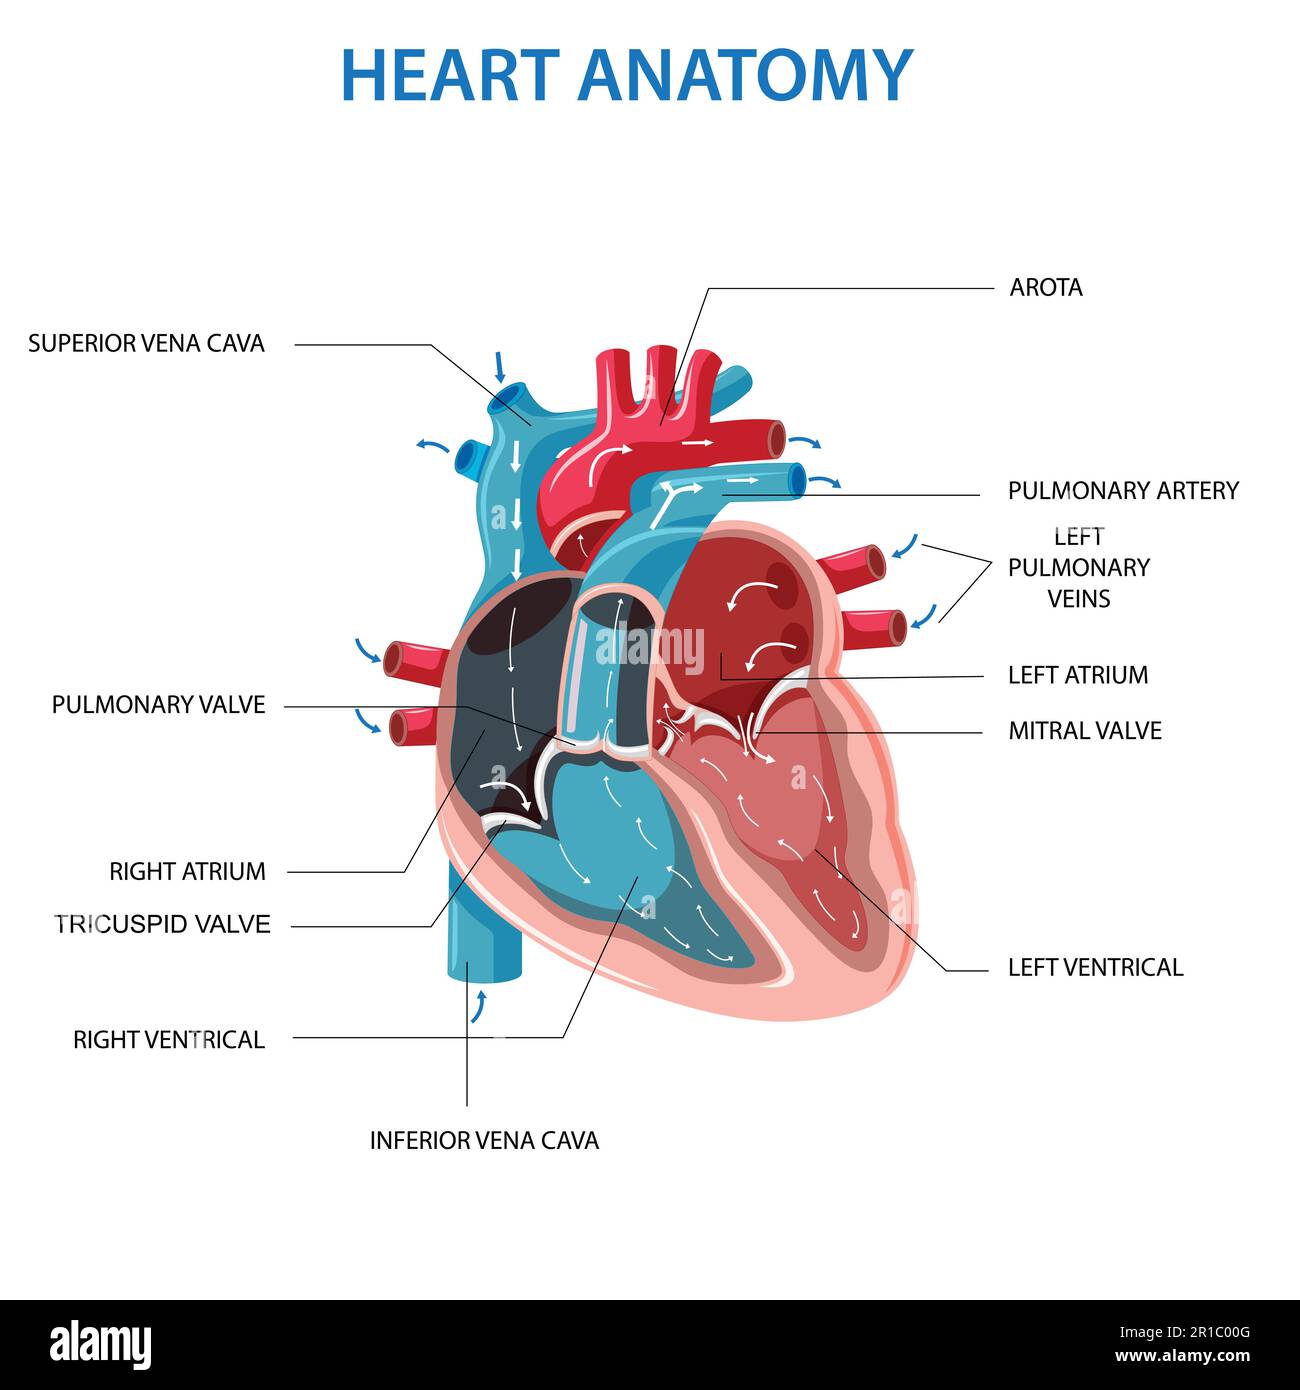

Anatomy of the human heart. Cross sectional diagram of the heart with main parts labeled. Human heart diagram Vector illustration. Educational diagram Stock Vectorhttps://www.alamy.com/image-license-details/?v=1https://www.alamy.com/anatomy-of-the-human-heart-cross-sectional-diagram-of-the-heart-with-main-parts-labeled-human-heart-diagram-vector-illustration-educational-diagram-image551609872.html

Anatomy of the human heart. Cross sectional diagram of the heart with main parts labeled. Human heart diagram Vector illustration. Educational diagram Stock Vectorhttps://www.alamy.com/image-license-details/?v=1https://www.alamy.com/anatomy-of-the-human-heart-cross-sectional-diagram-of-the-heart-with-main-parts-labeled-human-heart-diagram-vector-illustration-educational-diagram-image551609872.htmlRF2R1C00G–Anatomy of the human heart. Cross sectional diagram of the heart with main parts labeled. Human heart diagram Vector illustration. Educational diagram